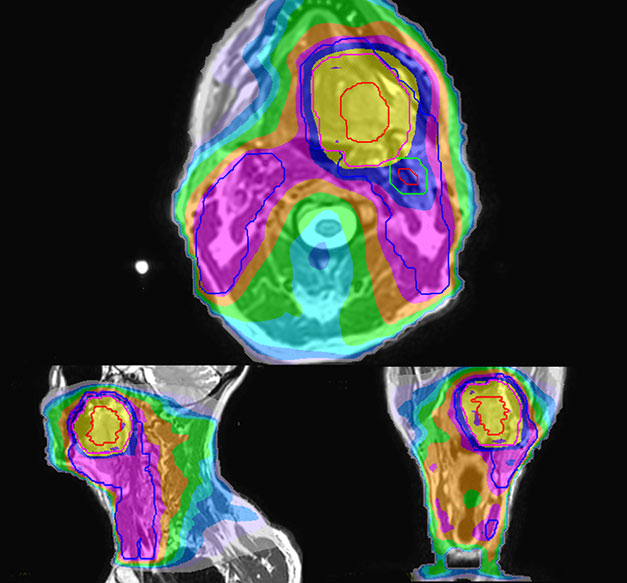

T2W 3D, 3D STIR and mDIXON MRI scans.

Comparison of CT simulation scan (left) and T2W 3D MRI (right)

MR-based target contouring on 3D T2W TSE in transversal, sagittal and coronal planes.

Personalized VMAT dose planned in Philips Pinnacle.